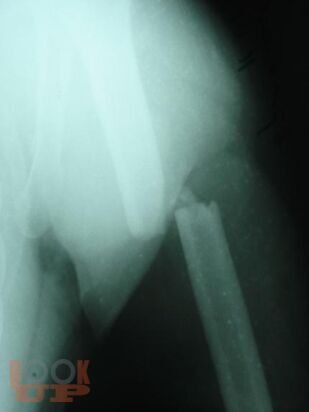

Учебно-методическое пособие содержит необходимую информацию для врачей по вопросам оказания специализированной помощи пострадавшим с тяжелой травмой костей нижних конечностей. Подробно освещены вопросы тактики оказания специализированной и высококвалифицированной помощи пострадавшим с тяжелыми монолокальными, множественными и сочетанными переломами костей конечностей в зависимости от периода развития травматической болезни. Отмечено, что в настоящее время оперативное лечение является основным при лечении переломов костей конечностей с учетом хирургической тактики контроля повреждения. Особое внимание уделено профилактике и лечению ранних осложнений тяжелых повреждений опорно-двигательного аппарата – синдрому жировой эмболии, тромбоэмболическим осложнениям. В пособии обобщен более, чем 20- летний опыт лечения пациентов с тяжелой травмой костей конечностей.